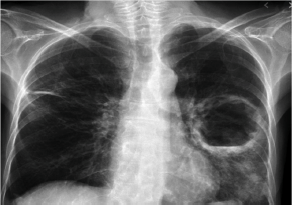

Homem de 40 anos, em situação de rua e etilista, é trazido por seus companheiros ao hospital. O paciente apresenta febre e perda de peso há 4 semanas, acompanhado de tosse com escarro purulento. Ao exame físico, emagrecido, em regular estado geral, com sinais vitais estáveis. Realiza RX tórax: